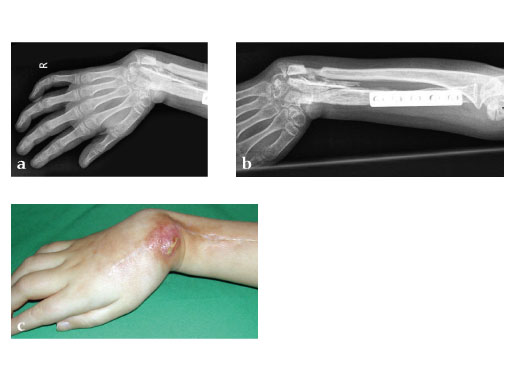

Female, 10 years, after bone tumor (Ewing's sarcoma) resection and allograft implantation, fistula to necrotic allograft.

Fig 1 ab: Preoperative x-rays.

Fig 1 c: Hand without any function.